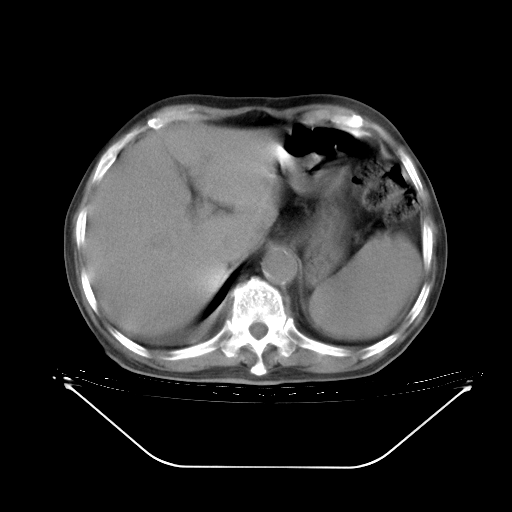

今天复查肺部CT,发现双肺广泛磨玻璃样改变。所以我把3月19日和5月9日相隔50天的肺部CT上传。请大家会诊。

5月9日肺部CT(在4月27日齐鲁医院肺部CT描述部分肺组织磨玻璃样改变,12天后肺组织广泛磨玻璃样改变)

大致读了系列胸部CT:纵隔窗无明显异常,肺窗:从4、27至今:主要是双肺中下野外带可见毛玻璃样改变,目前处于急性肺泡炎阶段,至于原因考虑1、结替组织或胶原血管性疾病所致?2、恶性疾病如恶组在肺部所致的表现或细支气管肺泡癌?3、药物或其它原因如肺蛋白沉着症所致肺泡炎目前不太可能?总之,明天就去请我院的呼吸科、感染科、血液科和临免专家会诊哈。